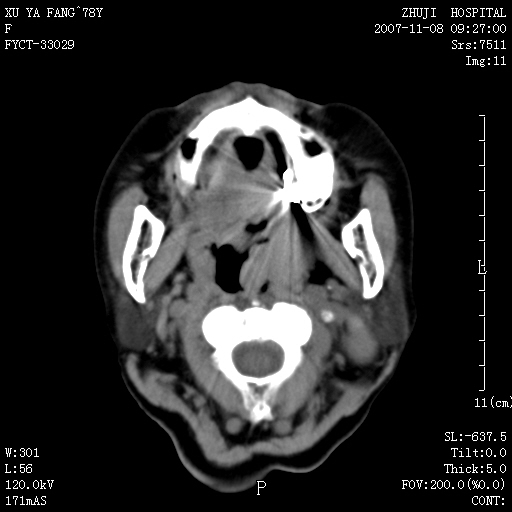

女性,78y,发现左侧扁桃体区肿大,表面糜烂.及颈部肿块一周.

左侧扁桃体恶性肿瘤伴淋巴结的转移

主要的鉴别是扁桃体的炎性增生与脓肿,假如没有淋巴结的肿大鉴别还是有困难的,增强脓肿是环形强化,临床症状也可鉴别

左侧扁桃体恶性肿瘤伴淋巴结的转移;考虑为扁桃体癌可能。此部位的恶性肿瘤以扁桃体癌和淋巴瘤多见,相对来说淋巴瘤范围较广泛些。有时两者区别较难,需要活检。

左侧扁桃体区软组织占位,强化后边界清晰,密度均匀,周围脂肪间隙清晰。周围淋巴结肿大。首先考虑扁桃体炎性增生,不排除扁桃体区的恶性肿瘤!!不知临床上有无发烧??/wbc是否增高??

左侧口咽侧壁巨大软组织肿块突入口腔,增强密度均匀,中度增强,左颈部多发肿大淋巴结,考虑左侧扁桃体恶性肿瘤(淋巴瘤还是癌不好鉴别)并淋巴结转移。 期待病理!